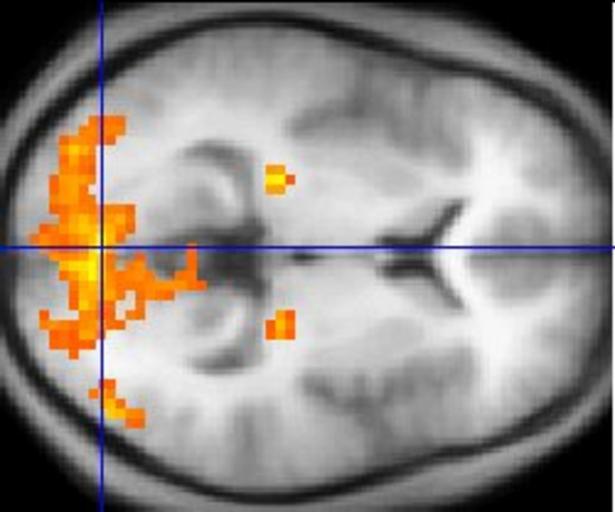

MAKE A MEME View Large Image Sample fMRI data Source http //en wikipedia org/wiki/Image FMRI jpg Public-domain copyright disclaimed Washington irving 07 49 8 Mar 2004 UTC This example of fMRI data shows regions of activation including primary visual cortex V1 BA17 ...

Keywords: FMRI.jpg Sample fMRI data Source http //en wikipedia org/wiki/Image FMRI jpg Public-domain copyright disclaimed Washington irving 07 49 8 Mar 2004 UTC This example of fMRI data shows regions of activation including primary visual cortex V1 BA17 extrastriate visual cortex and lateral geniculate body in a comparison between a task involving a complex moving visual stimulus and rest condition viewing a black screen The activations yellow-red are shown as is typical against a background based on the average structural images from the subjects in the experiment en English Wikipedia Washington irving Functional magnetic resonance imaging Magnetic resonance imaging of the brain Human brain horizontal section Visual cortex Lateral geniculate nucleus Functional magnetic resonance imaging.jpg Sample fMRI data Source http //en wikipedia org/wiki/Image FMRI jpg Public-domain copyright disclaimed Washington irving 07 49 8 Mar 2004 UTC This example of fMRI data shows regions of activation including primary visual cortex V1 BA17 extrastriate visual cortex and lateral geniculate body in a comparison between a task involving a complex moving visual stimulus and rest condition viewing a black screen The activations yellow-red are shown as is typical against a background based on the average structural images from the subjects in the experiment en English Wikipedia Washington irving Functional magnetic resonance imaging Magnetic resonance imaging of the brain Human brain horizontal section Visual cortex Lateral geniculate nucleus